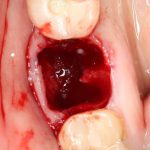

Рекомендации по установке имплантов. Для всех. Часть II.